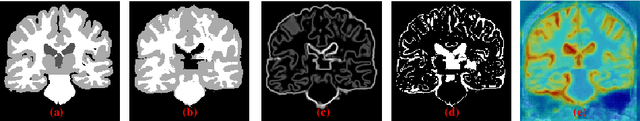

Abstract:Medical image segmentation is usually regarded as one of the most important intermediate steps in clinical situations and medical imaging research. Thus, accurately assessing the segmentation quality of the automatically generated predictions is essential for guaranteeing the reliability of the results of the computer-assisted diagnosis (CAD). Many researchers apply neural networks to train segmentation quality regression models to estimate the segmentation quality of a new data cohort without labeled ground truth. Recently, a novel idea is proposed that transforming the segmentation quality assessment (SQA) problem intothe pixel-wise error map prediction task in the form of segmentation. However, the simple application of vanilla segmentation structures in medical image fails to detect some small and thin error regions of the auto-generated masks with complex anatomical structures. In this paper, we propose collaborative boundaryaware context encoding networks called AEP-Net for error prediction task. Specifically, we propose a collaborative feature transformation branch for better feature fusion between images and masks, and precise localization of error regions. Further, we propose a context encoding module to utilize the global predictor from the error map to enhance the feature representation and regularize the networks. We perform experiments on IBSR v2.0 dataset and ACDC dataset. The AEP-Net achieves an average DSC of 0.8358, 0.8164 for error prediction task,and shows a high Pearson correlation coefficient of 0.9873 between the actual segmentation accuracy and the predicted accuracy inferred from the predicted error map on IBSR v2.0 dataset, which verifies the efficacy of our AEP-Net.